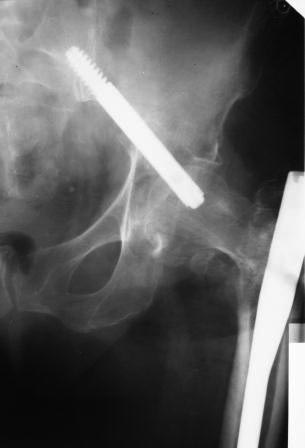

Доброе время суток коллеги. Прошу Вашей помощи, подскажите, как лучше

удалить винт.

пациентка по поводу вертельного перелома бедра оперирована 7 недель

назад, в быту ходила с нагрузкой. около 2-х дней назад упала. На снимках

вот такая картина. Сам ранее только читал, сейчас встретился воочию.